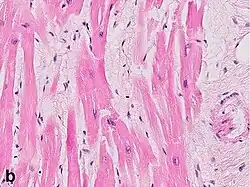

Under the microscope, myocardial infarction presents as a circumscribed area of ischemic, coagulative necrosis (cell death). On gross examination, the infarct is not identifiable within the first 12 hours.[22]

Although earlier changes can be discerned using electron microscopy, one of the earliest changes under a normal microscope are so-called wavy fibers.[23] Subsequently, the myocyte cytoplasm becomes more eosinophilic (pink) and the cells lose their transversal striations, with typical changes and eventually loss of the cell nucleus.[24] The interstitium at the margin of the infarcted area is initially infiltrated with neutrophils, then with lymphocytes and macrophages, who phagocytose ("eat") the myocyte debris. The necrotic area is surrounded and progressively invaded by granulation tissue, which will replace the infarct with a fibrous (collagenous) scar (which are typical steps in wound healing). The interstitial space (the space between cells outside of blood vessels) may be infiltrated with red blood cells.[22]

Stretched/wavy fibres | 1–2 h | ![]() | ||

Coagulative necrosis: cytoplasmic hypereosinophilia | 1–3 h | 1–3 days; cytoplasmic hypereosinophilia and loss of striations | > 3 days: disintegration | ![]() |